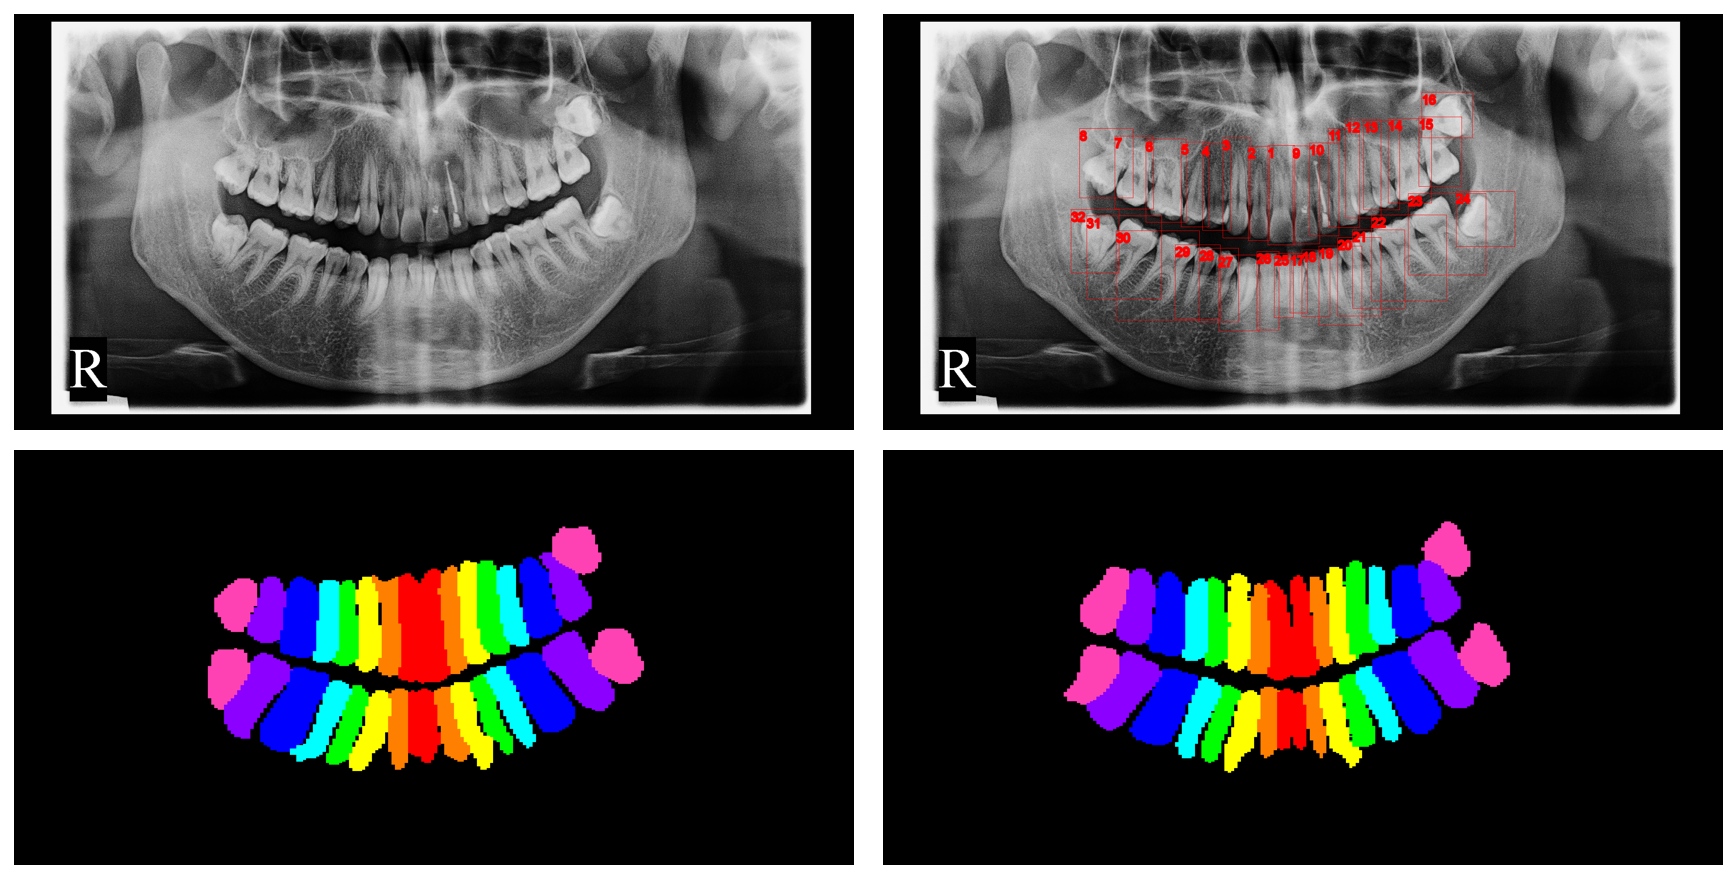

Quantitative results are shown in Fig. 2 3 4.

In Fig. 3, we show the cropped quadrants by the quadrant detection model in the first line, and their segmentation results in the following two lines. The second line is from U-Net, and the third line is from SE U-Net. Though there may be noises in the segmentation results, most of them can be removed by filtering the connected components. Meanwhile, the segmentation results do not have to be quite accurate, as they are converted to bounding boxes later.

Refer to caption

Figure 3: Cropped quadrants and their segmentation results